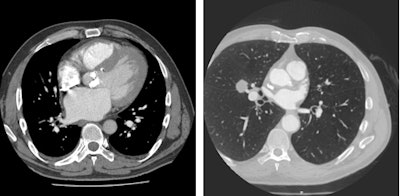

Left: Patient presenting with dyspnea. Contrast-enhanced CT chest demonstrates extensively calcified aortic valve with signs of heart failure. Right: Patient presenting with angina. The coronary CT angiography showed nonflow limiting coronary artery disease, but the full field-of-view reconstruction diagnosed lung cancer in the right middle lobe. Images courtesy of Dr. Edwin van Beek, PhD.Today the most relevant parameter for right ventricular function is measuring the ejection fraction by means of MRI. This parameter, which indicates how much percentage of its volume the heart can eject with each beat, is easy to measure and is an excellent parameter to predict outcome and to guide and monitor therapy, according to Dr. Jens Bremerich, head of the division of cardiothoracic imaging at the University Hospital of Basel in Switzerland. He will be presenting perspectives from cardiac imaging, specifically the role of the heart in cardiopulmonary disease.

Left: Patient with pulmonary hypertension. Conventional chest x-ray (A) shows enlarged pulmonary artery (white arrow); pulmonary circulation is compensated. Right: Contrast-enhanced CT yields enlarged right atrium (RA) and ventricle (RV). Hypertrophy of RV myocardium (arrowheads) indicate chronic RV pressure overload. Images courtesy of Dr. Jens Bremerich."This setup is a little more costly than usual, but it is very interesting and provides an excellent setting for cardiology and radiology residents to train," Bremerich said. "I think all hospitals should strive to carry out dual reading and reporting in selected cases, and in general there should be a low threshold for exchange with the referrer in cardiothoracic imaging."